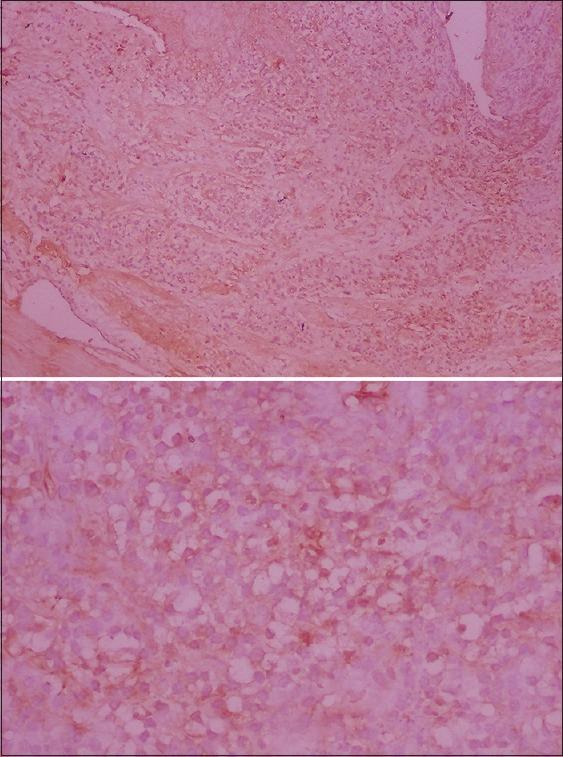

Thirty-five patients selected for the study and divided into control group (10) and study group (25) consisting of phenytoin (10); cyclosporin (10) and nifedipine (5) induced gingival enlargement. Gingival overgrowth index of Seymour was used to assess overgrowth and allot groups. Under LA, incisional biopsy done, tissue sample fixed in 10% formalin and immunohistochemically evaluated for the presence of IL-6 using LAB-SA method, Labeled- Streptavidin-Biotin Method (LAB-SA kit from Zymed- 2(nd) generation LAB-SA detection system, Zymed Laboratories, CA). The results of immunohistochemistry were statistically analyzed using Kruskaal-Wallis and Mann-Whitney test.

RESULTS

The data obtained from immunohistochemistry assessment shows that drug-induced gingival overgrowth (DIGO) samples express more IL-6 than control group and cyclosporin expresses more IL-6 followed by phenytoin and nifedipine.

选取35例患者进行研究,分为对照组(10例)和研究组(25例),研究组包括苯妥英钠所致牙龈增生(10例)、环孢素所致牙龈增生(10例)和硝苯地平所致牙龈增生(5例)。采用西摩牙龈增生指数评估增生情况并分组。在局部麻醉下进行切口活检,将组织样本固定于10%福尔马林中,采用LAB-SA法(来自Zymed的第二代LAB-SA检测系统,Zymed Laboratories,加利福尼亚州)免疫组织化学评估IL-6的存在情况。免疫组织化学结果采用Kruskaal-Wallis和Mann-Whitney检验进行统计学分析。

结果

免疫组织化学评估获得的数据显示,药物性牙龈增生(DIGO)样本表达的IL-6比对照组多,环孢素表达的IL-6最多,其次是苯妥英钠和硝苯地平。

结论